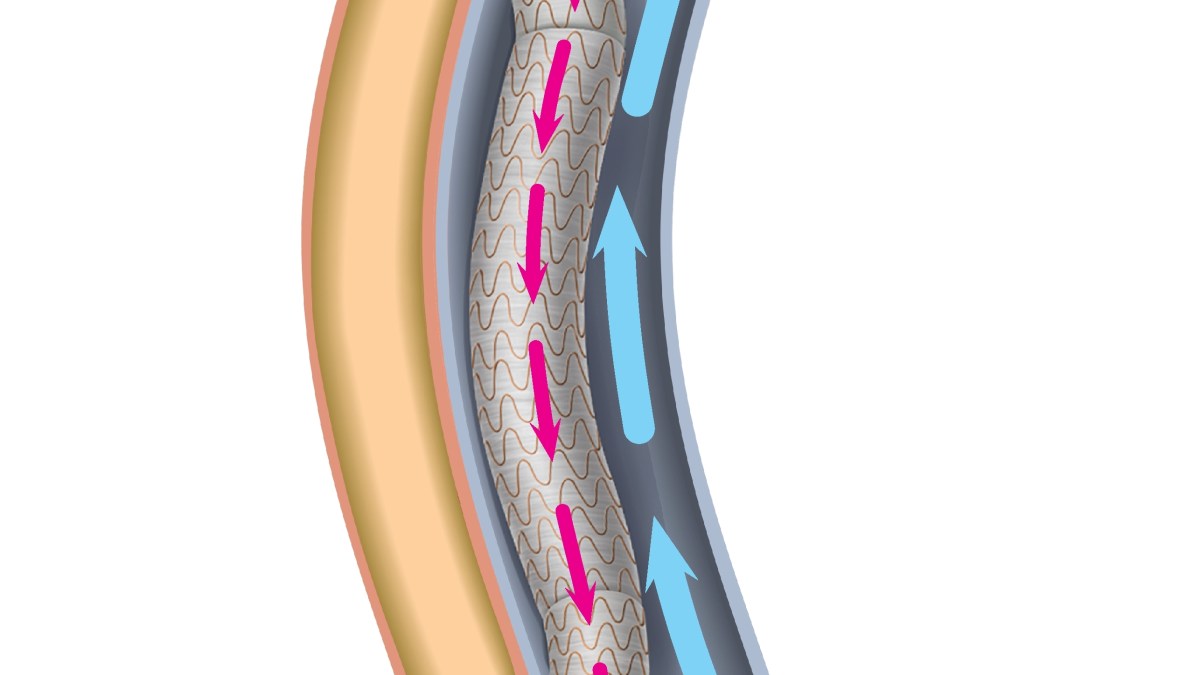

وتعيد عملية “مجازة الشريان التاجي” توجيه مسار الدم حول انسداد في الشريان الذي يحمله إلى القلب، وفي هذه العملية الجديدة، تم إدخال الأدوات الجراحية وتمريرها من خلال وعاء دموي في ساق المريض، وفقا لتقرير نُشر في مجلة “سيركيوليشن كارديوفاسكيولار إنترفينشنز” (Circulation: Cardiovascular Interventions).